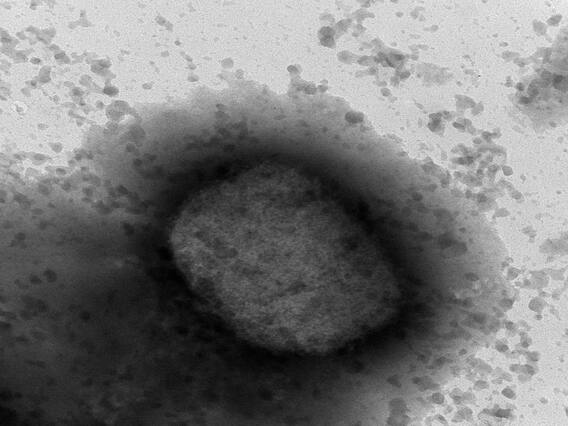

Covid Monkeypox: కరోనా వైరస్ (Coronavirus)తో కలవరపడుతోన్న ప్రపంచ దేశాలను మంకీపాక్స్ (Monkeypox) గడగడలాడిస్తోంది. తాజాగా మంకీపాక్స్ కేసులు ప్రపంచవ్యాప్తంగా వేగంగా పెరుగుతున్నాయి. ఇప్పటికే ఈ వైరస్ 75 దేశాలకు వ్యాపించడంతో ప్రపంచ ఆరోగ్య సంస్థ (WHO) అత్యవసర స్థితిని ప్రకటించింది. అయితే ఇలాంటి సమయంలో కరోనా సోకిన ఓ వ్యక్తికి మంకీపాక్స్ వచ్చింది. ఇలా జరగడం ఇదే తొలిసారని వైద్యులు చెబుతున్నారు.

ఇప్పటికే 75 దేశాలకు మంకీపాక్స్ వ్యాపించింది. ముఖ్యంగా మంకీపాక్స్ కేసుల్లో దాదాపు 95 శాతానికిపైగా కేసులు స్వలింగ సంపర్కుల్లోనే వస్తున్నట్లు నివేదికలు వస్తున్నాయి. ప్రపంచవ్యాప్తంగా ఇప్పటివరకు 16 వేల కేసులు నమోదుకాగా ఐదుగురు చనిపోయారు.